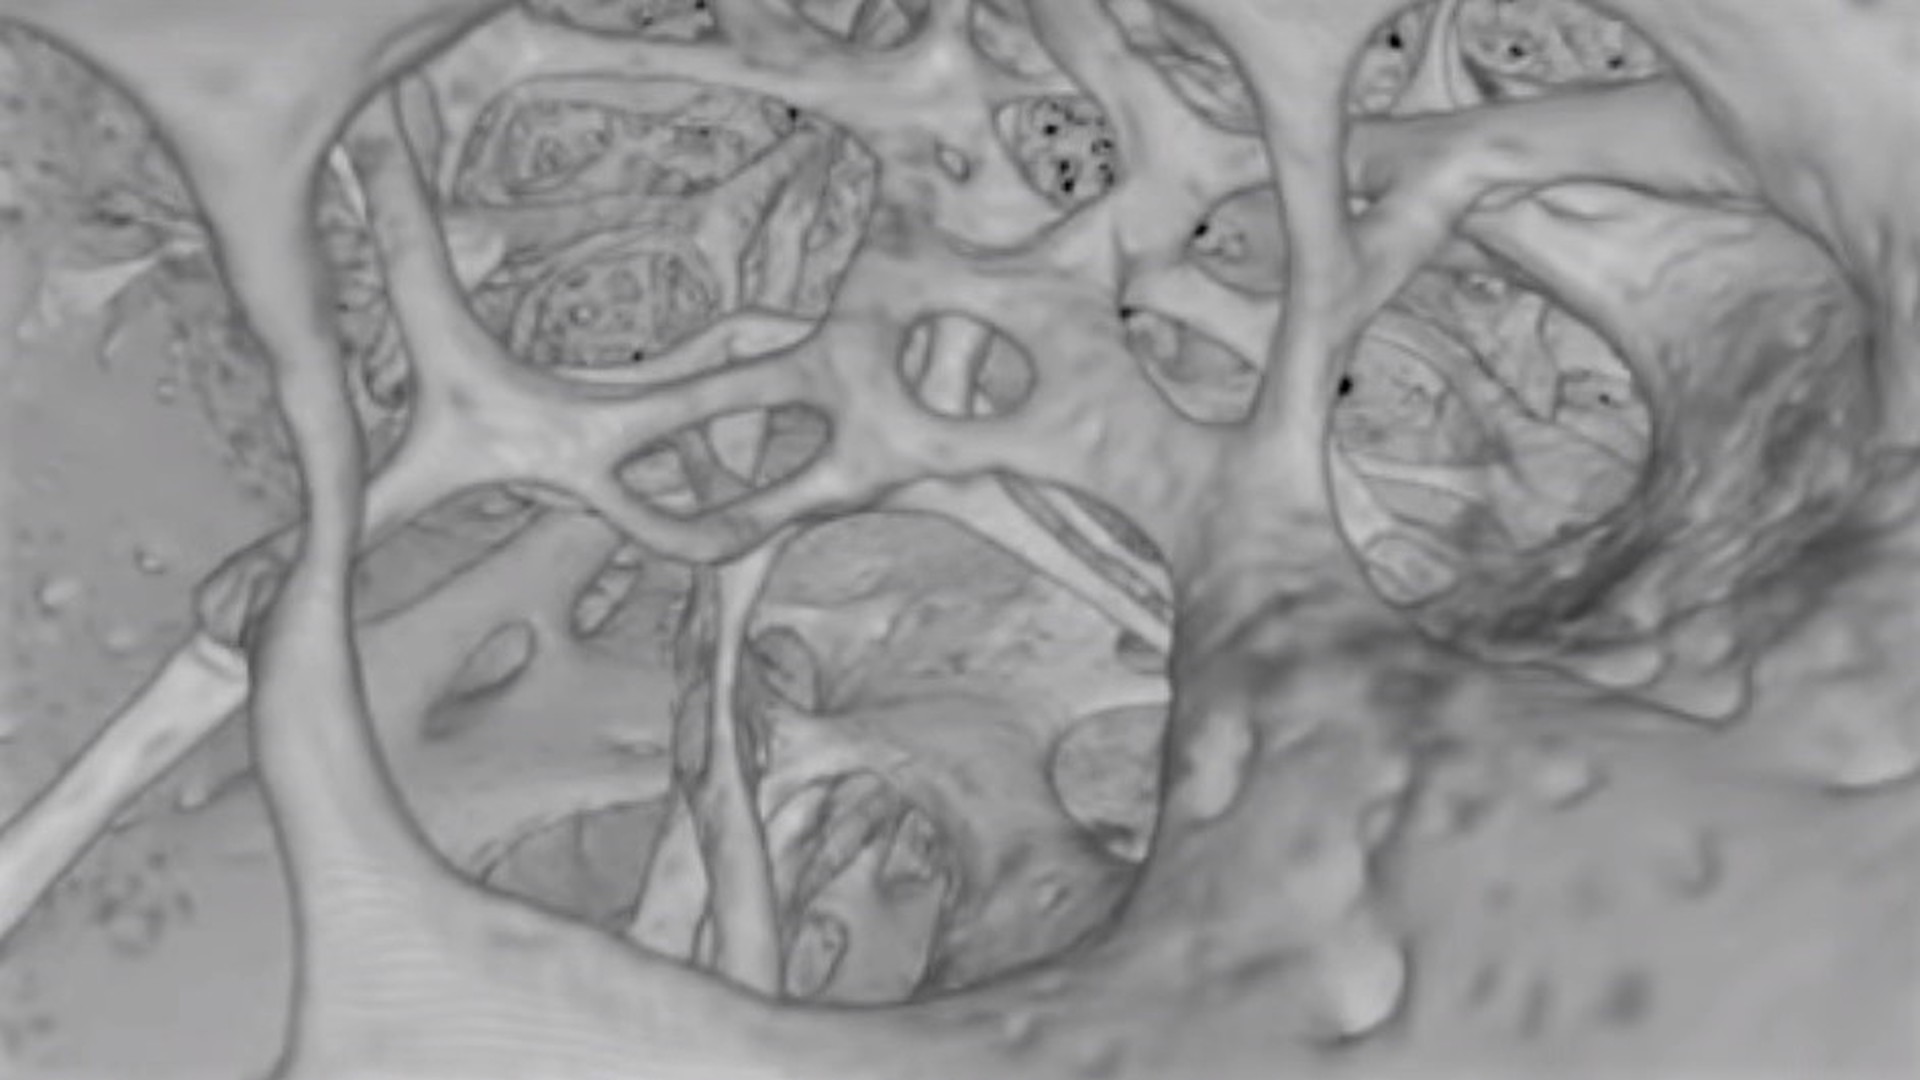

В костной ткани есть капилляры

В костной ткани есть капилляры 111 фото